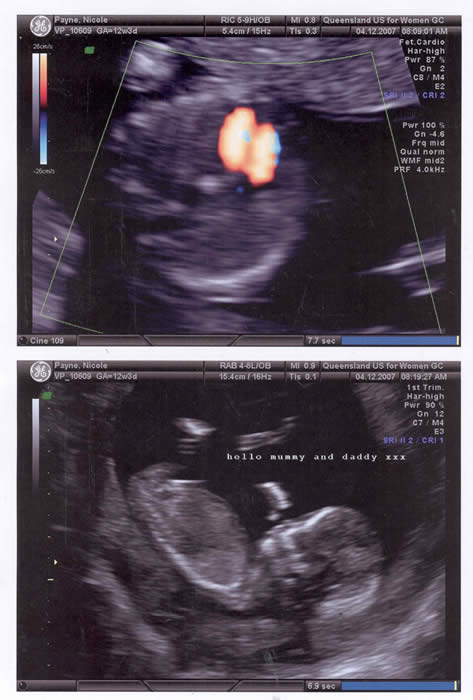

Can you see my Grand-daughter - she is healthy, happy and growing!!!

Our Baby at 13 weeks